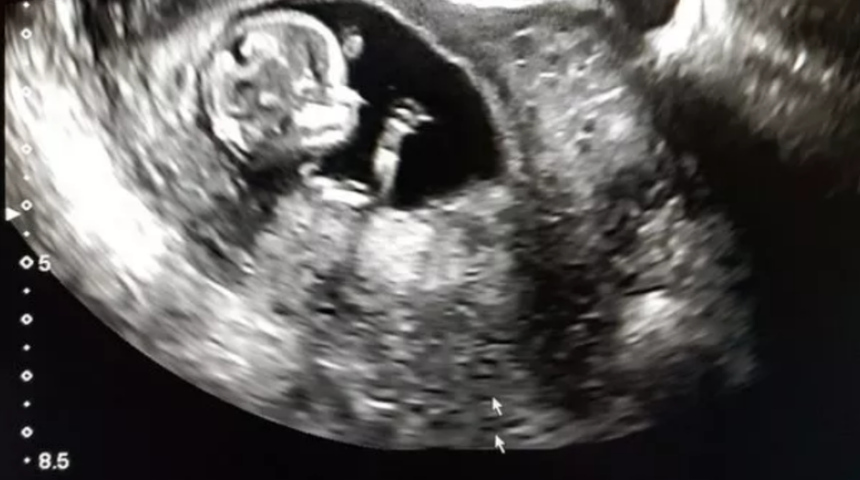

İran'da cinsel organı olmadan doğan bebek tüm dünyayı şaşırttı. Bebeğin annesi yaptığı açıklamada gayet normal bir hamilelik geçirdiğini söyledi. Bebek iki testisi olmasına rağmen penis veya vajinaya sahip olmadan doğdu. Cinsel organı olmadan doğma vakalarının oldukça nadir olarak 30 milyonda bir görüldüğünü belirten doktorlar bebeğe organ yapacaklarını açıkladı. Aphallia adı verilen bu durumun tıbbi literatürde 100'den az vaka belgelendiğini söylendi.

Bebeğin idrarını nasıl yapacağı merak konusu olmuşken anüsünden yaptığı açıklandı. Aphallia, hamileliğin ilk birkaç ayında genital organların rahimde normal şekilde gelişmemesi durumunda ortaya çıkar. Erkeklerin iki penisle doğduğu, diphaliye neden olan benzer bir süreçtir. Radyoloji Vaka Raporları dergisinde vakayı bildiren sağlık görevlileri , çocuğun normal olarak "iyi bir genel durumda" doğduğunu söyledi.